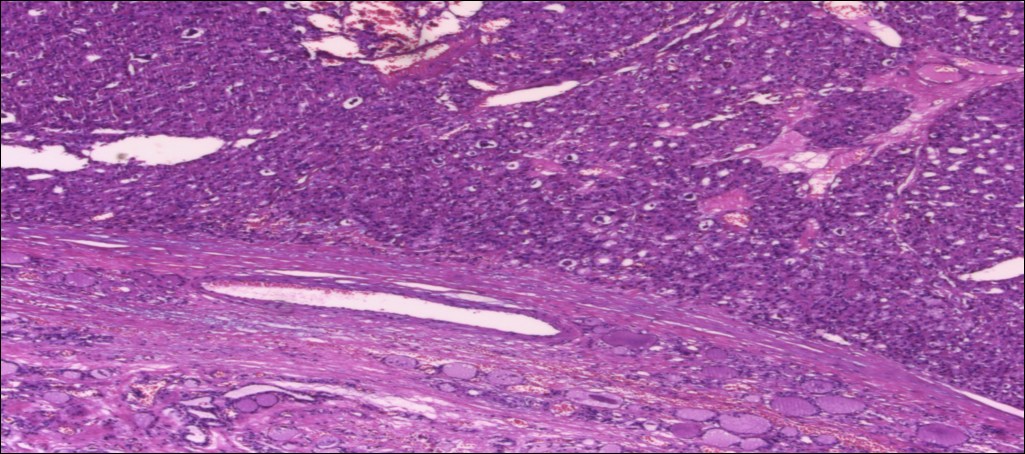

甲状腺嗜酸性细胞腺瘤

(甲状腺右叶及峡部):暗褐结节,直径6cm,包膜完整

肿物包膜完整,镜下未见明确包膜、脉管侵犯

镜下可见包膜,脉管侵犯!